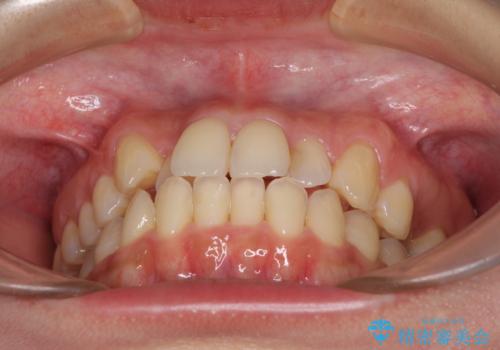

- 前歯のデコボコを気にして来院された患者様です。

上顎右側犬歯が八重歯になっており、それによって奥歯が前方に移動しているため、右側の咬み合わせの改善が必要と判断されました。

マウスピース矯正では改善に時間がかかる、あるいは改善しきれない可能性があることを伝えたところ、短期間で確実に治療ができるワイヤー矯正を選択されました。